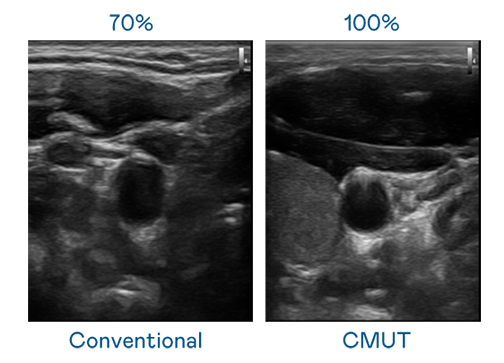

CMUT 技术是一种用电容式微机电元件来产生超音波讯号的技术。与传统 PZT 压电式技术相比,CMUT 频宽增加 30%,更宽频的超音波讯号让影像解析度大幅提升,是实现高影像品质医疗超音波扫描、促进精准医疗发展的关键技术。

大频宽带来超清晰影像

超音波影像的解析度高低,首先取决于探头能发出的讯号频宽。mile米乐 CMUT 可提供高清晰的超音波讯号,提供高频宽、高灵敏度、影像纹理细节更高的超音波影像,协助医护人员缩短影像判读时间及利用精准的医疗影像进行诊断。